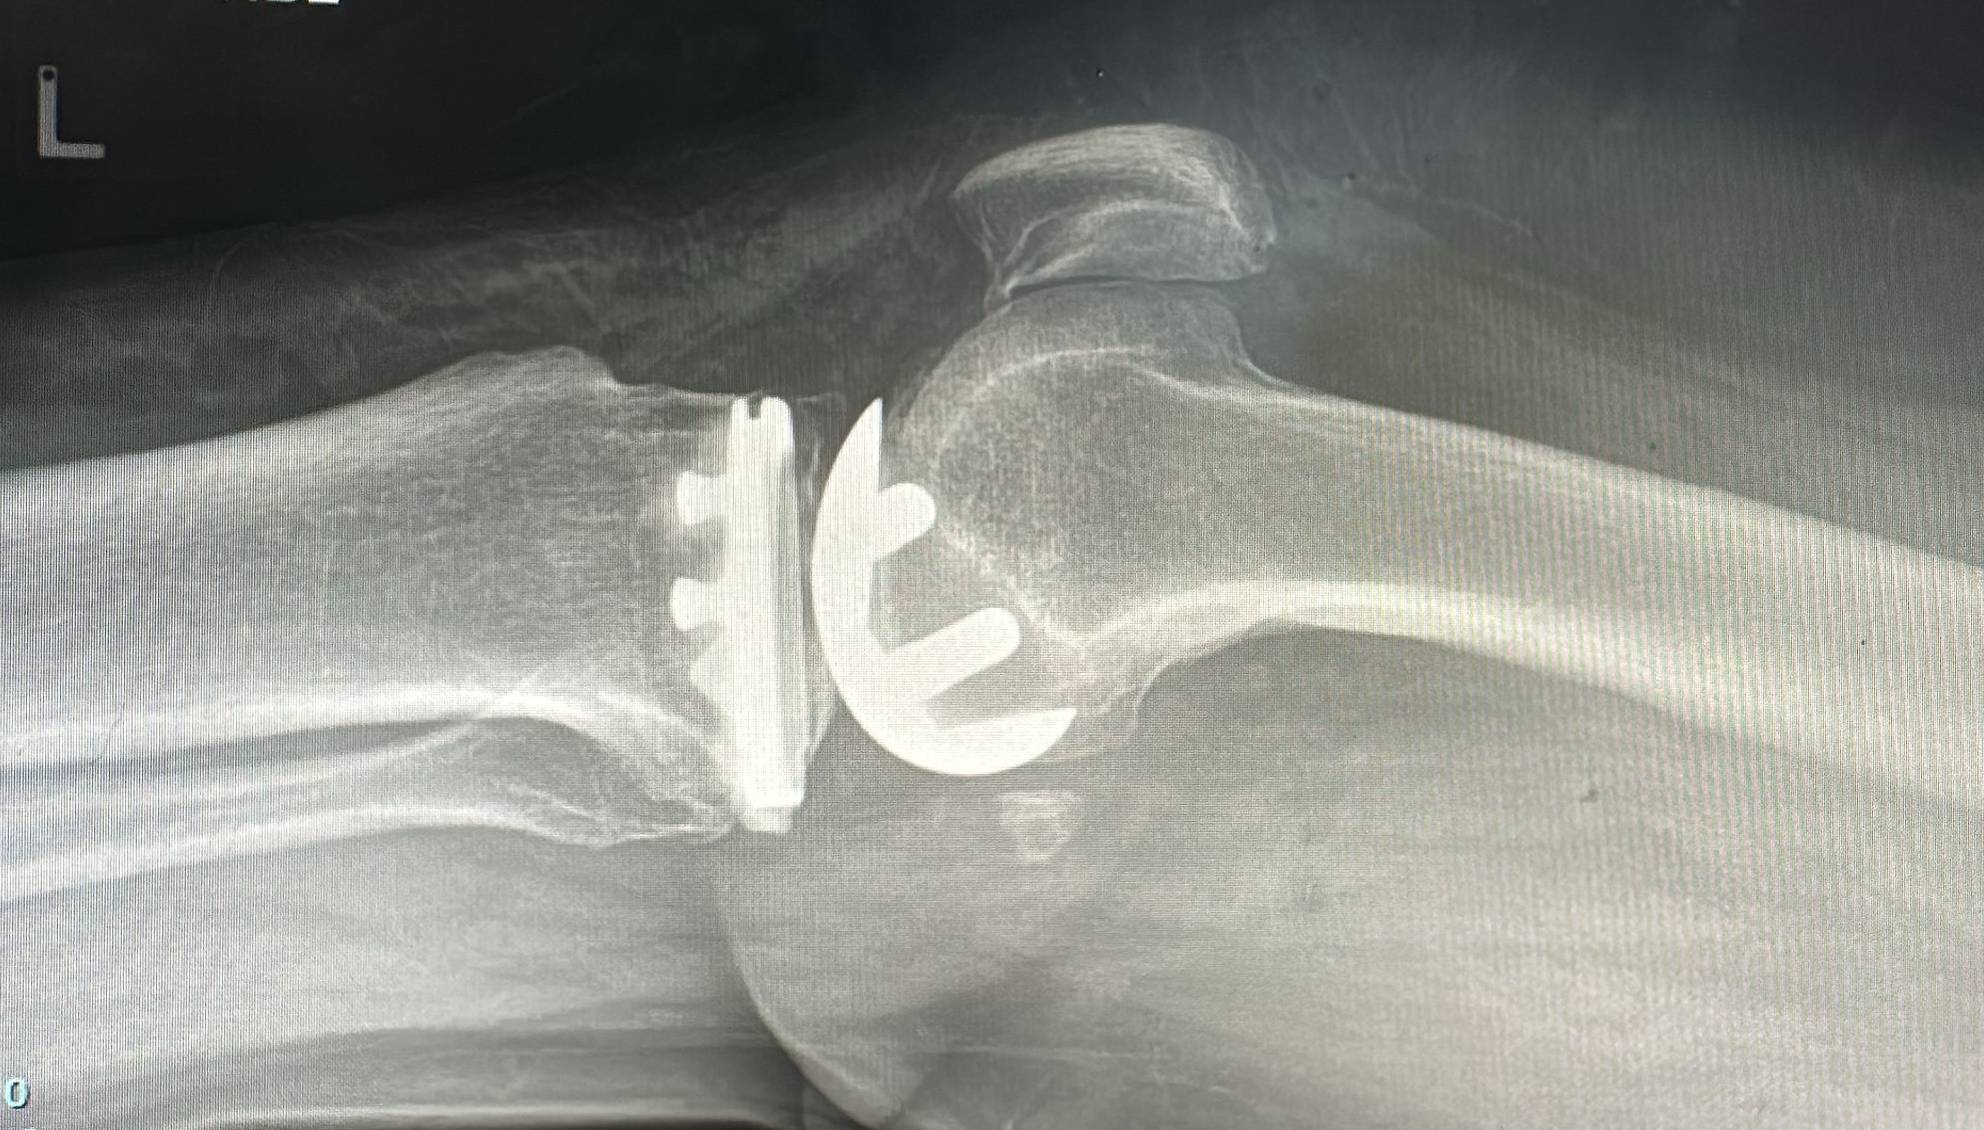

Zimmer Persona: Advanced Partial Knee Replacement

The Zimmer Persona platform delivers bone-preserving, ligament-sparing solutions for patients with isolated knee compartment arthritis. Enjoy faster recovery and superior outcomes.

Zimmer Persona is an advanced partial knee replacement system designed for patients with arthritis limited to one compartment of the knee. It preserves healthy bone and natural ligaments while providing excellent pain relief and functional outcomes.

- ✓Zimmer Persona implant insertion and alignment